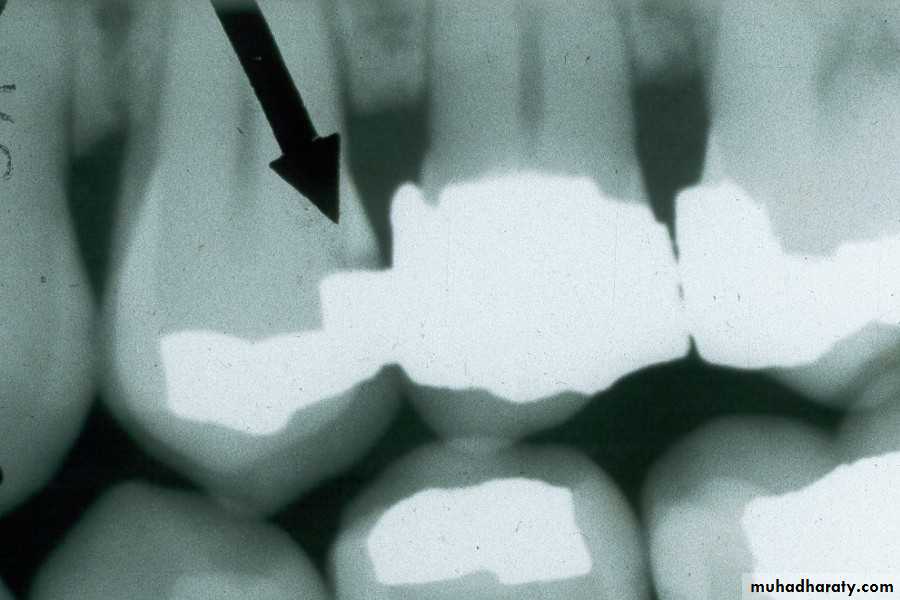

Interproximal Caries (Advanced)

extends to or through the DEJ and into dentin but does not extend through dentin more than half the distance toward the pulpAdvanced Interproximal Caries

An advanced carious lesion, which extends through the dentino-enamel junction (DEJ) and into dentin, seen on the distal surface of the mandibular first molar.

Advanced Interproximal Caries

Advanced lesion identified by arrows.